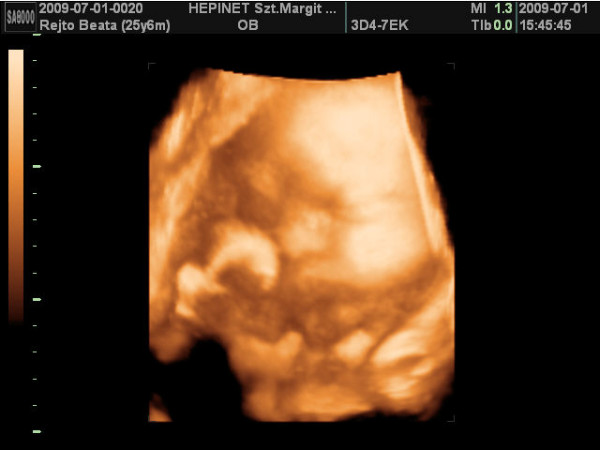

ma vagyok 6 hetes 5 napos.a jó hír,hogy szombaton már láttam és hallottam életemben először a kicsi szívhangját!!!!!!![]()